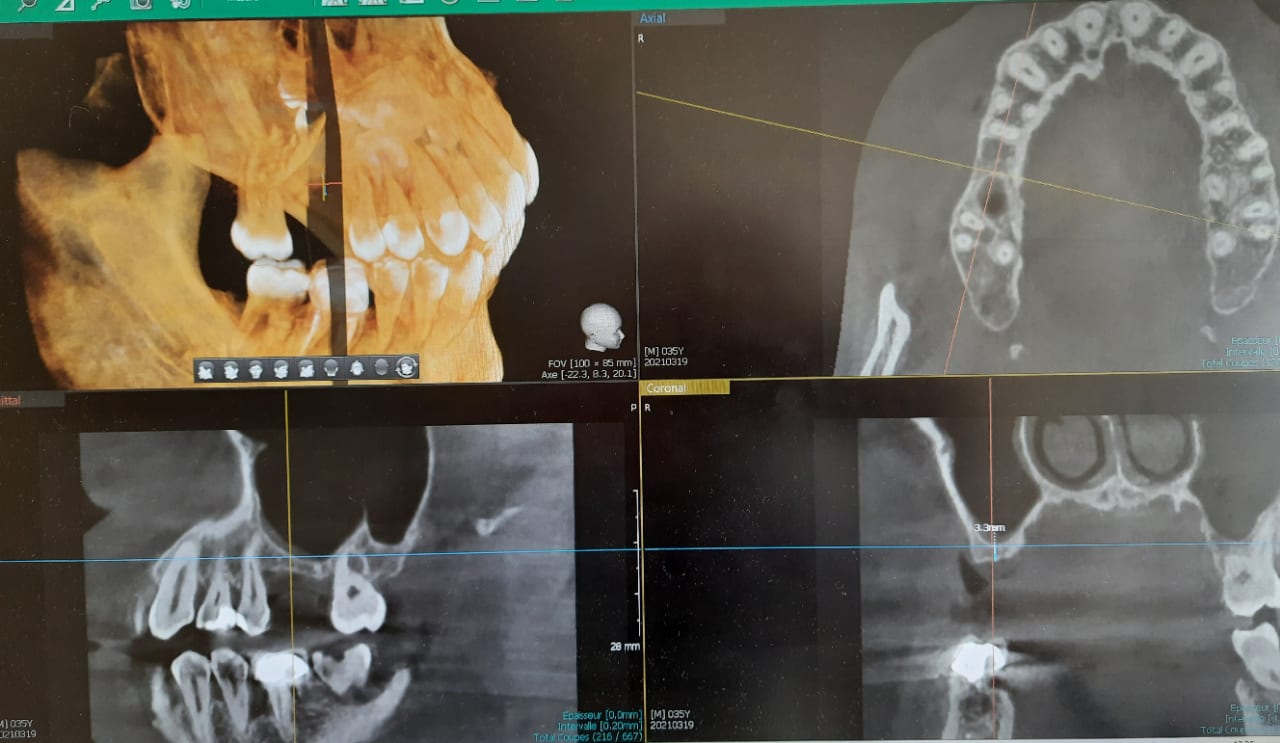

je souhaiterais votre avis sur ce cas :

plutôt un summers moins traumatisant pour le patient (et pour moi)

car une seule dent, muqueuse avec une légère épaisseur et quand meme 3 petits mm pour stabiliser mon implant

ou bien le sinus lift classique pour lequel je suis un peu moins à l aise , plus traumatisant mais plus fiable .

Pour info : quelle est ton système d'imagerie CBCT ? Je trouve les clichés de bonne qualité Merci

sinon mon cone beam cest un vatech et j en suis super content l image est vraiment belle et là cest juste une photo d ecran prise de mon tel .

le vrai cliché est beaucoup mieux defini.